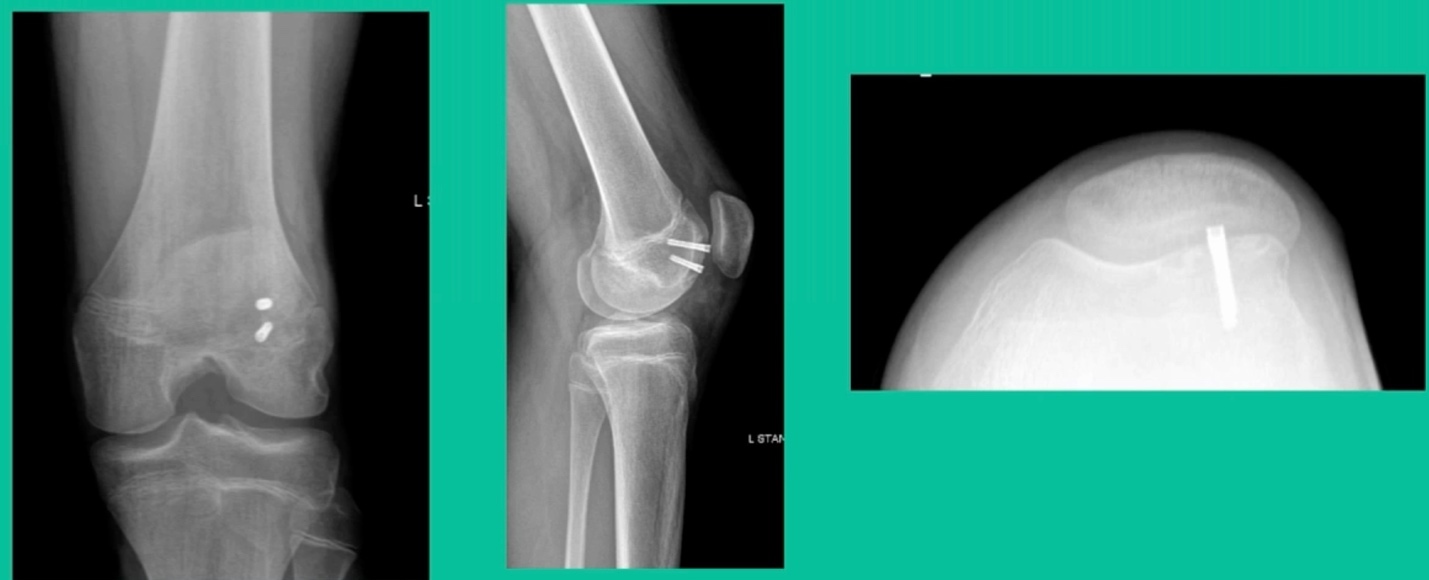

The challenge is this. This series of patients were populated by early decisions to treat when patients don’t have symptoms. That’s a problem in my mind. Post-Op, they protect their weight-bearing. That’s actually treatment. These are often smaller lesions of the medial femoral condyle. They do really well. That being said, it’s an option. It’s not my option. My option for someone who’s macroscopically unstable is we use biocomposite screws (Figure 4).

These biocomposite screws will hang around for upwards of a year. So, they’re not innocuous, and you’ve got to bury their heads. But we drill it, we tap it, and we stabilize it, and then we drill from the side in an effort to promote further biology. This is analogous to just arthroscopic fixation, but I don’t go back, and I don’t remove the screws. Then I’ll typically take a K-wire from the side after I place these screws. I keep them non-weight-bearing for eight weeks. I don’t remove it. I wait four months before they go back to high-impact activities like this patient did here.

What are the outcomes? Very, very favorable. We had 87% survivorship using a biocomposite screw. Would I use it for a macroscopically unstable one? I wouldn’t. I would tell you that the biomechanics are not nearly as good, and it is not innocuous. If you leave the head proud, this will scratch the tibia and cause a railroad track there. You must bury them, but don’t take them out.